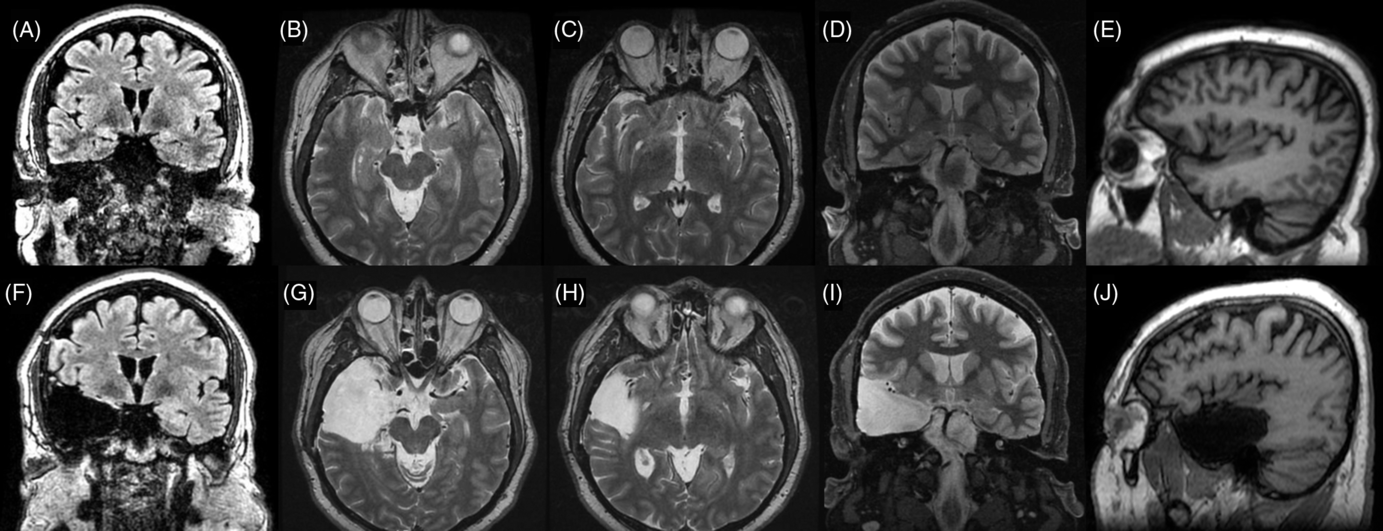

Case 1: Thirty-one-year-old, right-hand dominant male. He began having seizures at the age of 3 years. At the time of surgical evaluation, he presented two types of seizures. First type was nocturnal focal aware seizures with prominent type-1 hypermotor features.Reference Rheims, Ryvlin and Scherer12 Second type was less frequent, consisted of daytime focal unaware seizures with behavioral arrest and blurry vision that occasionally progressed to bilateral tonic-clonic (BTC) seizures. Neuropsychological evaluation showed left language dominance and non-lateralizing frontotemporal dysfunction. MRI was normal. Scalp EEG revealed bilateral frontotemporal spikes and seizures with activity more prominent in the right frontal lobe. The patient underwent invasive EEG recording in the form of subdural strips covering bifrontal and bitemporal regions on two occasions. On the first occasion, the patient had no seizures while admitted to the epilepsy unit. On the second occasion, orbitofrontal spikes were found, and supplementary strips in the orbitofrontal area were implanted. Four seizures were captured from the right orbitofrontal area and one from the right mesial temporal region. A staged resection was proposed: first, the orbitofrontal region was partially resected, but the patient continued having seizures with the same frequency and semiology. SEEG was then performed covering the right temporal and orbitofrontal regions: three independent seizures originating in the right mesial temporal region and in the ipsilateral orbitofrontal cortex, adjacent to the previous resection, were found. The patient underwent a right-sided ATL with additional orbitofrontal resection (Figure 1A). He has been seizure-free with persistence of occasional auras with a follow-up time of 2.4 years.

Case 2: Thirty-two-year-old, right-hand dominant male with a history of reflex epilepsy triggered by eating for 5 years. The patient sustained somatosensory seizures with oral automatisms, left head and eye deviation, and postictal right-hand nose wiping. Neuropsychological testing was normal with left language lateralization. MRI revealed hippocampal sulcus remnant cysts on the right. These were considered incidental findings with no abnormal changes in hippocampal volume or signal. PET scan was normal. Scalp EEG showed right temporal seizures extending to the suprasylvian region. The patient was investigated with SEEG, and seven seizures with simultaneous onset in the right hippocampus and inferior insula were recorded (Figure 2). The patient was offered a right ATL with partial resection of the insular cortex. The latter was performed with the aid of neuronavigation, accessing the insula transpially and resecting the tissue that overlapped the active contacts of the depth electrodes involved (Figures 1B, 3A–J and 4A and B). Patient has remained seizure-free since surgery, 1.3 years ago.

Case 3: Twenty-seven-year-old, right-hand dominant male with seizure onset at the age of 14 years. He experienced focal unaware sensory seizures with gustatory auras, left-head version and dystonic posturing. Ictal spitting was frequently present and BTC seizures were common. Neuropsychological evaluation lateralized language to the left hemisphere and was otherwise normal. MRI showed no focal abnormality. PET scan showed hypometabolism of the right temporal lobe. VEEG lateralized seizures to the right hemisphere but was non-localizing. SEEG identified 12 seizures arising from the right hippocampus and simultaneously in the right anterior and posterior insular electrodes (Figure 5). The surgery was a right ATL with partial insulectomy (Figure 1C). Patient is seizure-free after 1.3 years of follow-up.

Case 4: Forty-year-old, right-hand dominant female with seizure onset when she was 9 months old. Semiologically, she experienced focal emotional seizures with impaired awareness. Seizures began with fear/anxiety and occasionally with paresthesias in both her feet. This would typically progress to slurred speech or vocalization, rightward head deviation, clonic jerking of the left arm, and progression to BTC seizures. Neuropsychology revealed left language dominance which was confirmed during Wada test, and bilateral temporal memory dysfunction. MRI revealed bilateral hippocampal volume reduction. The scalp VEEG found left anterior temporal onset in all recorded seizures. The decision was made to proceed with invasive investigations using bilateral subdural strips, which revealed left-sided temporal lobe seizures. A left ATL was performed, which rendered her seizure-free for 3 years. After seizure recurrence, seizures seemed to have the same semiology. EEG showed mostly posterior left temporal seizures. A new invasive investigation with depth electrodes was suggested. The SEEG study revealed numerous spikes and electrographical seizures arising in the posterior hippocampus. Six clinical seizures were obtained with clear onset over the left anterior-inferior insula. Based on these findings, an additional anterior insulectomy was performed (Figure 1D). Despite having occasional auras, patient has remained seizure-free after 4.5 years following the procedure.

Case 5: Forty-six-year-old, left-hand dominant female with seizure onset at the age of 2 months. She had congenital hydrocephalus, which required shunting in the neonatal period. She experienced nocturnal progression to BTC and daytime focal unaware seizures with behavioral arrest and right-hand automatisms. Neuropsychology identified left language dominance and left frontal and neocortical dysfunction with memory preserved bilaterally. MRI showed moderately enlarged ventricles, but no focal abnormalities were found. Abundant right temporal spikes as well as right frontotemporal seizures were identified in scalp EEG. Five seizures were recorded during the SEEG study, four of them with onset in the right amygdala and hippocampus, and one seizure with clear onset in the right orbitofrontal cortex (posterior gyrus rectus and adjacent orbital gyrus). Unfortunately, during the fifth seizure, the electrodes were accidentally explanted. Despite this, sufficient information was obtained to recommend a right ATL with orbitofrontal corticectomy (Figure 1E). Patient is seizure-free at 1.3 years following the surgery.

Case 6: Forty-year-old, right-hand dominant female with seizure onset at the age of 27 years. A right-sided insular cavernoma was found and a resective surgery was undertaken initially. Seizures recurred within 3 months, mostly consisting of behavioral arrest, bimanual automatisms, and left arm jerking. Neuropsychology identified atypical language laterality and memory preserved bilaterally. MRI showed hemosiderosis in the right insula. Right frontotemporal spikes were identified in scalp EEG but no seizures were captured. She underwent invasive recording of the right frontotemporal region via subdural electrodes. Numerous seizures arose from the right mesial temporal region. An ATL with visual exploration of the insula was conducted; however, no tissue was resected in the latter structure. The patient was seizure-free for 3 years, after which the episodes recurred with the same semiology and became increasing in frequency after 5 years. Forty-seven seizures were recorded during the SEEG study, all arising from the right insula. A supplementary insular corticectomy was performed (Figure 1F) and the patient is free of disabling seizures at 4.7 years following the surgery (Engel 1c).

Figure 1: Illustration of resected tissue for each case in each surgery. (A) Case 1: Right anterior temporal lobectomy + orbitofrontal resection. (B) Case 2: Right anterior temporal lobectomy + posterior inferior insular resection. (C) Case 3: Right anterior temporal lobectomy + inferior insular resection. (D) Case 4: Left anterior temporal lobectomy + anterior inferior insular resection. (E) Case 5: Right anterior temporal lobectomy + orbitofrontal resection. (F) Case 6: Right anterior temporal lobectomy + subtotal insular resection.